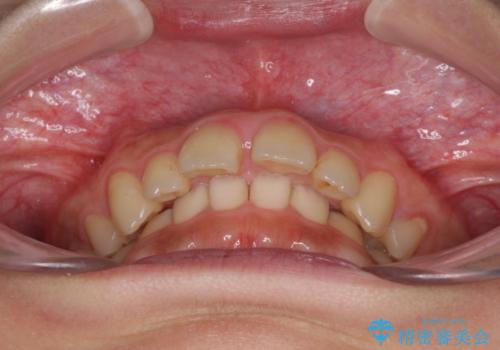

- 深い咬み合わせと上顎前歯の突出感を気にして来院された患者様です。

正面や横からの写真ではきれいに治っており、患者様は大変満足のいく仕上がりとなりましたが、深い咬み合わせの改善は不十分で、奥歯の咬み合わせも改善させることができませんでした。

インビザラインは、咬合力の強い方ですと、奥歯が歯肉内にめり込んでしまうため、前歯が強く接触してしまうことがあります。

こちらの方は、奥歯はしっかりと噛んだのですが、歯肉にめり込んでしまったことで、歯肉が腫れやすくなってしまいました。